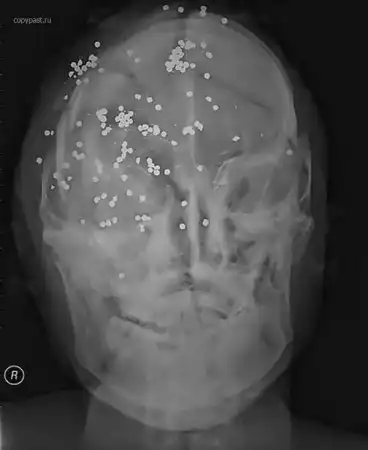

Убийство. Множественные выстрелы в голову

Ранения дробью в голову